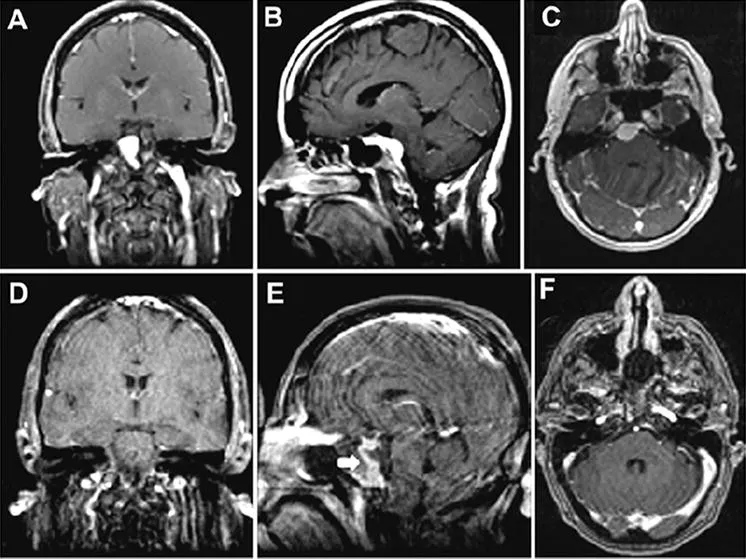

一位52岁女性病患呈现复视及间歇性头痛。体检时,患者右眼外展受损。MRI显示右岩斜交界处肿块均匀强化,伴有广泛的斜坡附着,提示脑膜瘤(图A-C)。我们进行了部分岩尖切除术。术后核磁共振证实全切除(图D-E),并无脑损伤。注:增强鼻中隔皮瓣用于重建。病人在术后第7天出现脑嵴液漏。手术检查显示,这是由鼻中隔皮瓣的右上角移位引起的,但此移位已成功且永久地矫正。病人手术后恢复良好,复视消失,外展正常。

图示:术前图像显示起源于上斜坡的岩斜脑膜瘤。肿瘤均匀强化,脑干受压,无海绵窦侵犯。术后图像显示肿瘤完全切除。E:图中的白色箭头示增强的重建的鼻中隔,提示其血供保留。